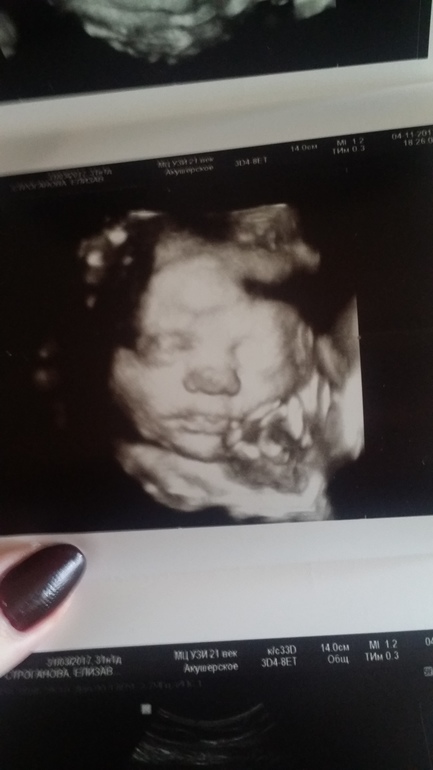

3D УЗИ. Детки рождаются как на снимке?

УЗИ, КТГ, доплерДелали недавно узи (31 неделя). Стало интересно, дети действительно внешне такие как на фото?))

Наш карапуз на фото😍

У меня 2 д снимок в в 33 нед дочкиных... очень похожа родилась... у подруг тоже...